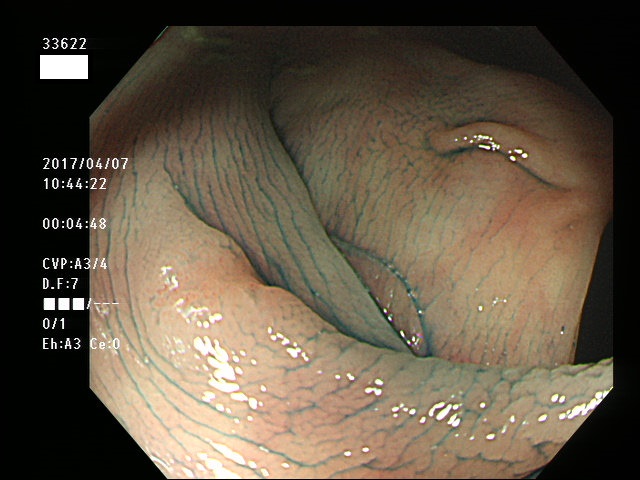

上記100名より抽出した平坦・陥凹型腺腫(=癌化の危険が高いが見落としやすい病変)の内視鏡写真

33600 33603 33606 33607(SSA/Pのみ) 33608 33609 33610 33613 33616 33617 33618 33620 33622 33624 33625 33626